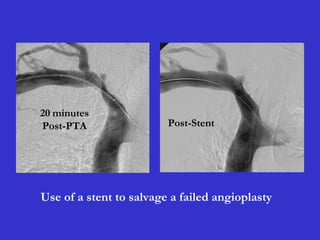

Post-PTA 10 minutes 15 minutes

Post-PTA

20 minutes

stent

positioning

Return of original stenosis

due to elastic recoil phenomenon.

Post-PTA Post-Stent

Use of a stent to salvage a failed angioplasty